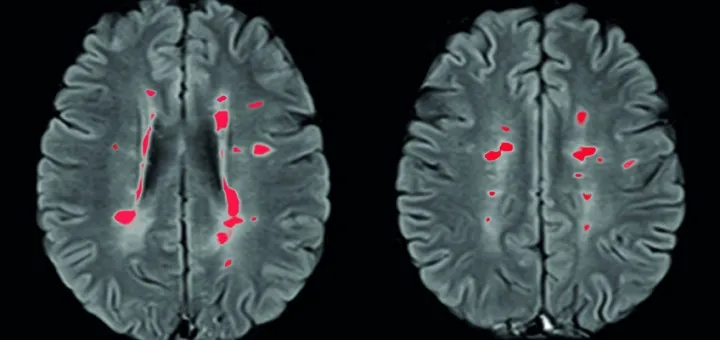

SCLEROSI MULTIPLA

Si può sbloccare il meccanismo che ripara il danno della mielina

Le cellule progenitrici riparanoil danno della sclerosi multipla